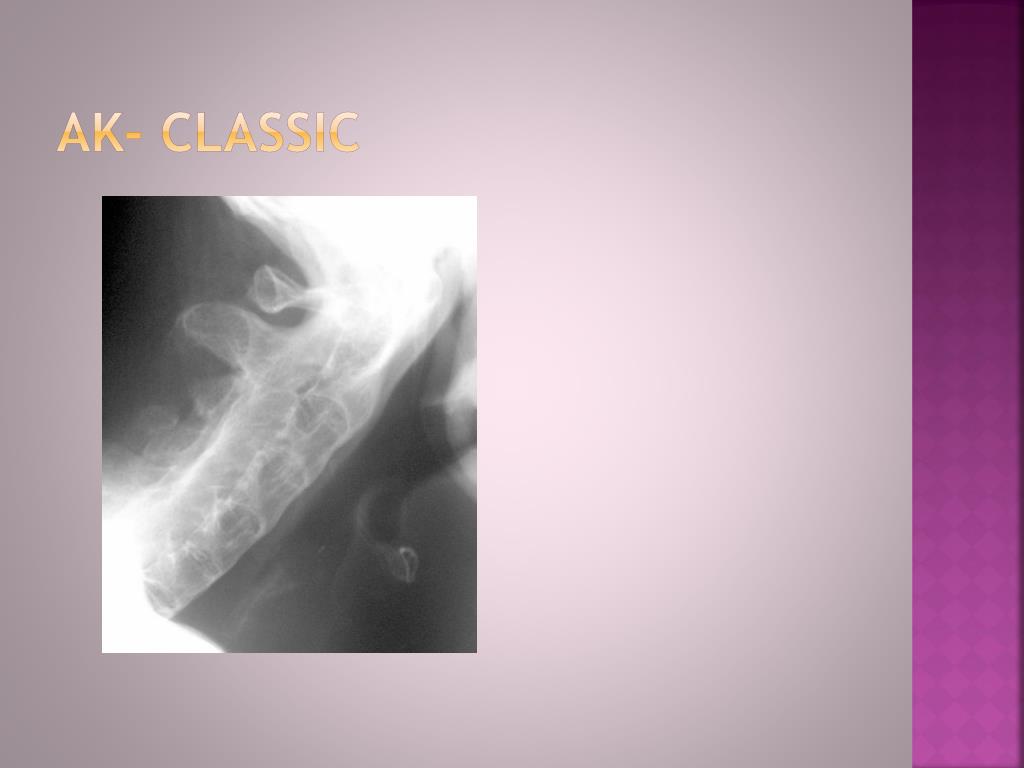

12. AK- classic

13. AK